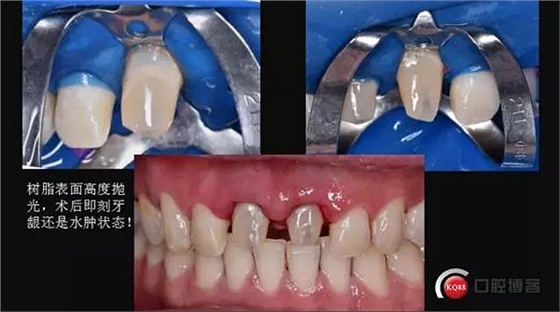

粘結(jié)前的準備

酸蝕時間死髓牙60秒,活髓牙五到十秒,上障比較困難全程在強吸下操作,確保粘結(jié)強度

本次使用的是bisco雙固化樹脂,60秒后初步固化,12號刀片和牙線去除多余粘結(jié)劑

去除隔離膜,涂布阻氧劑后各個方向固化,每個方向60-90秒

術(shù)后即刻照,口腔衛(wèi)生宣教!